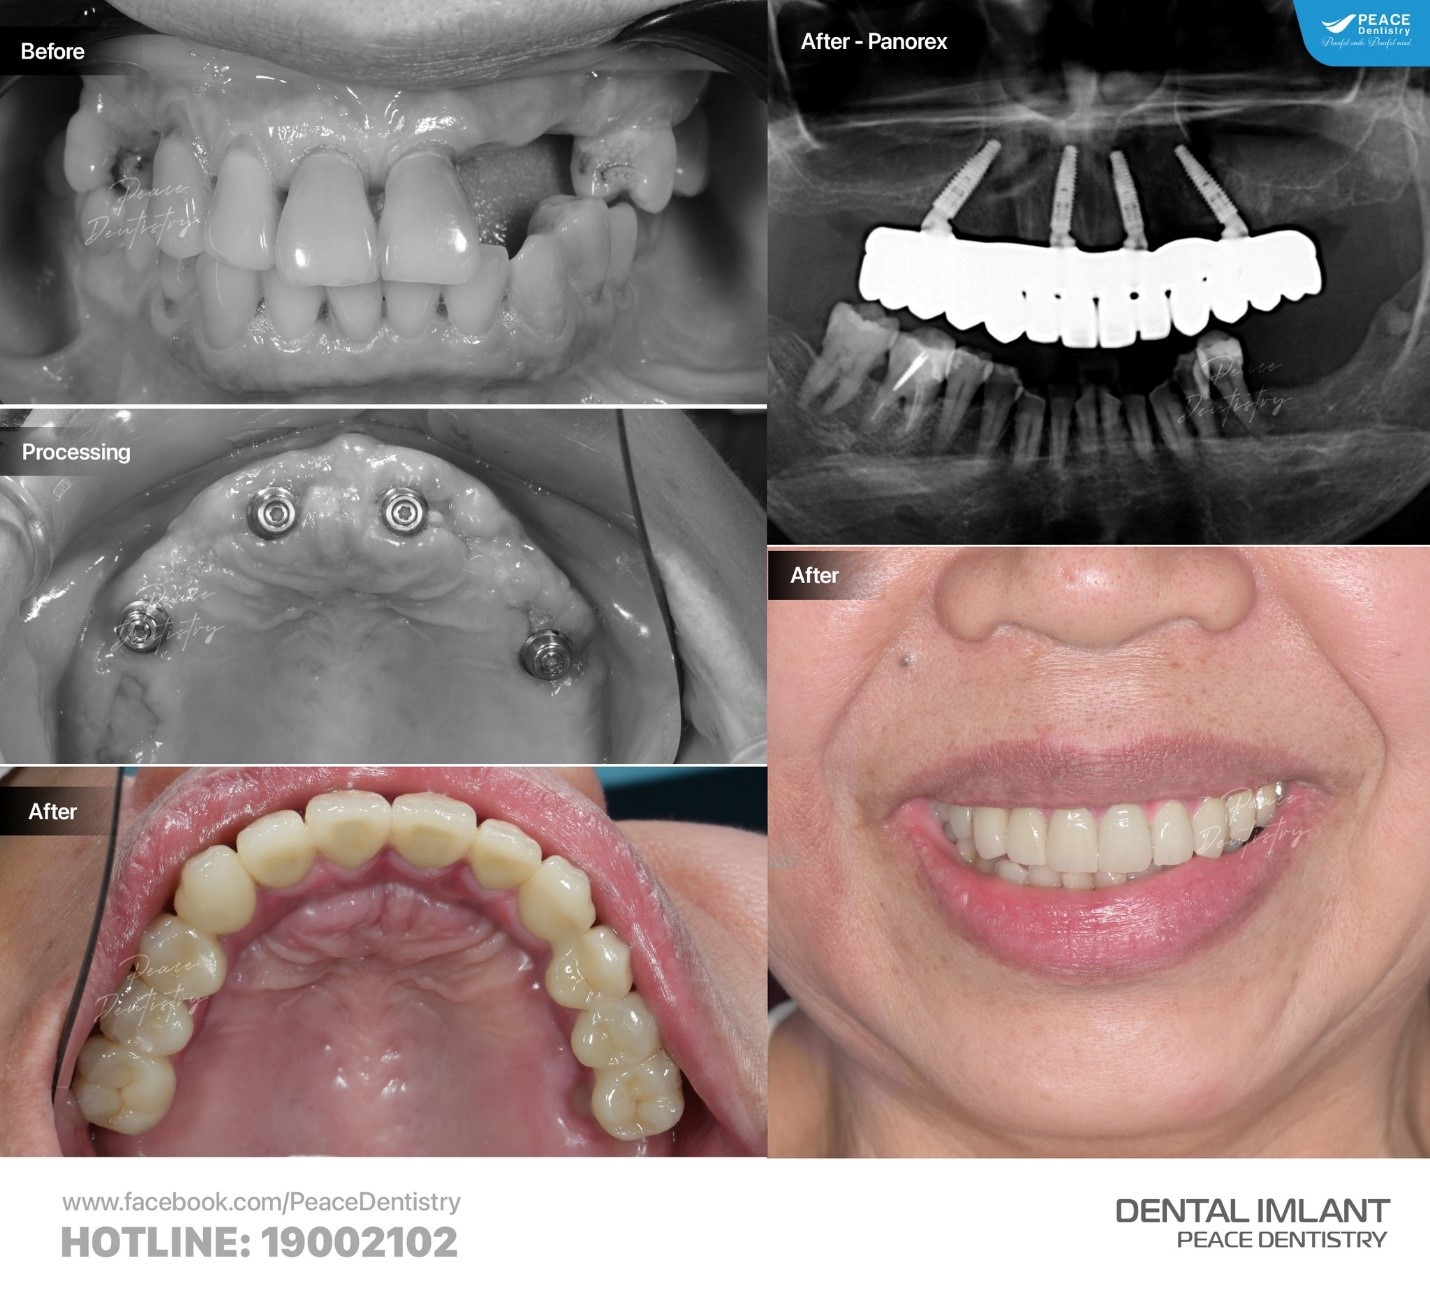

(Kết quả trồng răng Implant được điều trị tại Peace Dentistry)(**)